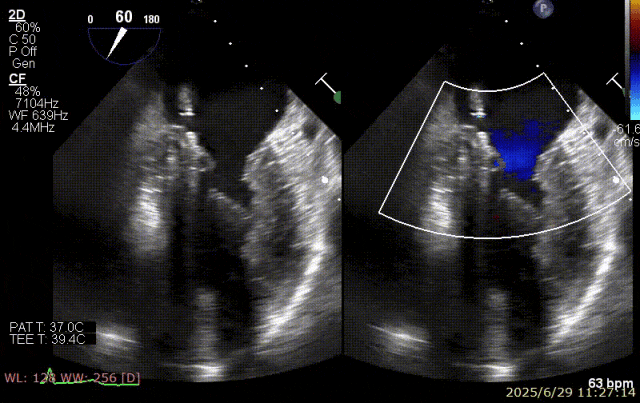

术前超声

患者术前 TEE 可见 P3 区脱垂二尖瓣环前后径(AP)约 37 mm,CC 径约 41 mm,瓣叶无明显钙化及裂隙,后瓣瓣尖探及一长约 9 mm 短带样回声漂附,二尖瓣口面积约 5.3 cm²。

经我院心脏超声检查提示:左房室增大伴二尖瓣后瓣脱垂(P3 区,腱索断裂)并重度关闭不全(Carpentier IIb 型,反流分级 4+);符合高血压性心脏病改变;少至中等量心包积液;左室舒张功能降低,收缩功能测定在正常范围并呈假性高排表现。